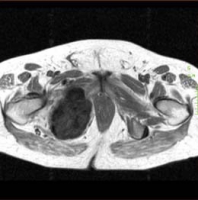

- T1 : signal intermédiaire ou bas signal

- T2 : zones de haut signal (cartilage) et de bas signal (zone minéralisée)

- T1 gadolinium : prise de contraste des septas, des anneaux et des arcs

* pas de prise de contraste au niveau des zones de nécrose, kystiques mucoïdes, du cartilage hyalin